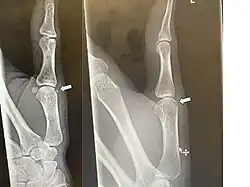

Avulsion fracture of the proximal middle phalanx on the palm side | |

An avulsion fracture is a bone fracture which occurs when a fragment of bone tears away from the main mass of bone as a result of physical trauma. This can occur at the ligament by the application of forces external to the body (such as a fall or pull) or at the tendon by a muscular contraction that is stronger than the forces holding the bone together. Generally muscular avulsion is prevented by the neurological limitations placed on muscle contractions. Highly trained athletes can overcome this neurological inhibition of strength and produce a much greater force output capable of breaking or avulsing a bone.